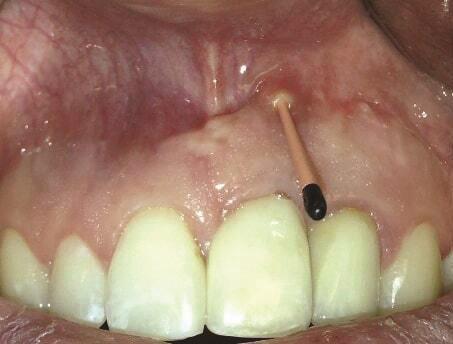

Пациент 1: Пациентка 30 лет с неосложненным медицинским анамнезом обратилась с имплантатом № 2.1, у которого диагностирован ретроградный периимплантит. Зуб № 2.1 был заменен имплантатом 8 лет назад из-за травмы в анамнезе и неудачного лечения корневых каналов. Имплантат демонстрировал периапикальную рентгенопрозрачность со свищевым ходом, ведущим к верхушке имплантата № 2.1 (Фото 1 и Фото 2). У пациентки была высокая линия улыбки с более длинными клиническими коронками зубов №№ 2.1 и 2.2 по сравнению с №№ 1.2 и 1.1 (Фото 1 и Фото 2).

Фото 1 и Фото 2. Случай 1: Первоначальная клиническая картина с гуттаперчевым штифтом, установленным в апикальный свищ зуба № 2.1 (Фото. 1); рентгеновский снимок, показывающий гуттаперчевый штифт, ведущий к периапикальному поражению (Фото. 2).